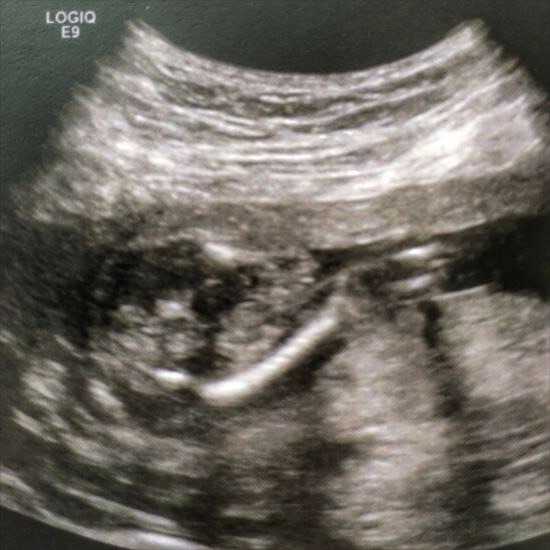

Any guesses on this? Tech said 50% girl.

Bottom on the left, legs squished crossed (unfortunately) heading out to the right

Not a great picture because of position. If I had to guess I'd say maybe girl 60/40

From what I see, things are squished, but I'd guess girl. :)

Slight girl lean.